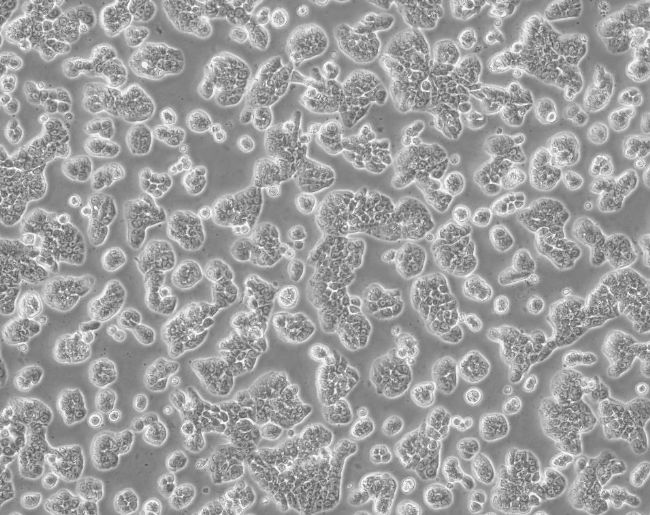

▲細胞正常生長形態(tài)照片

該細胞成簇生長,細胞胞體黑點較多是正常現(xiàn)象。細胞很難生長到100%,當匯合達到80%時,即可傳代。